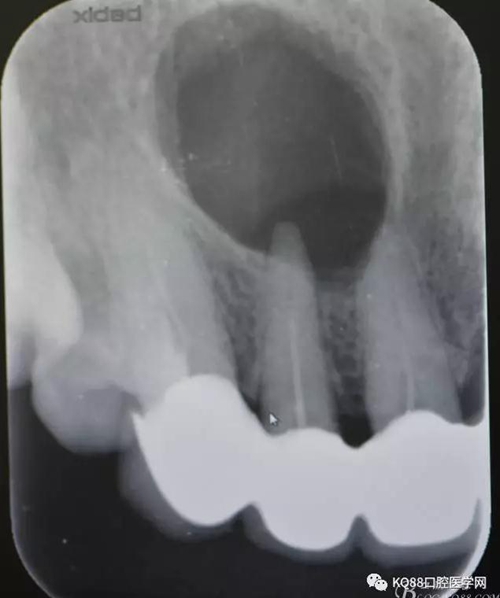

圖1.術(shù)前的根尖片影像檢查:11、12根管治療不完善